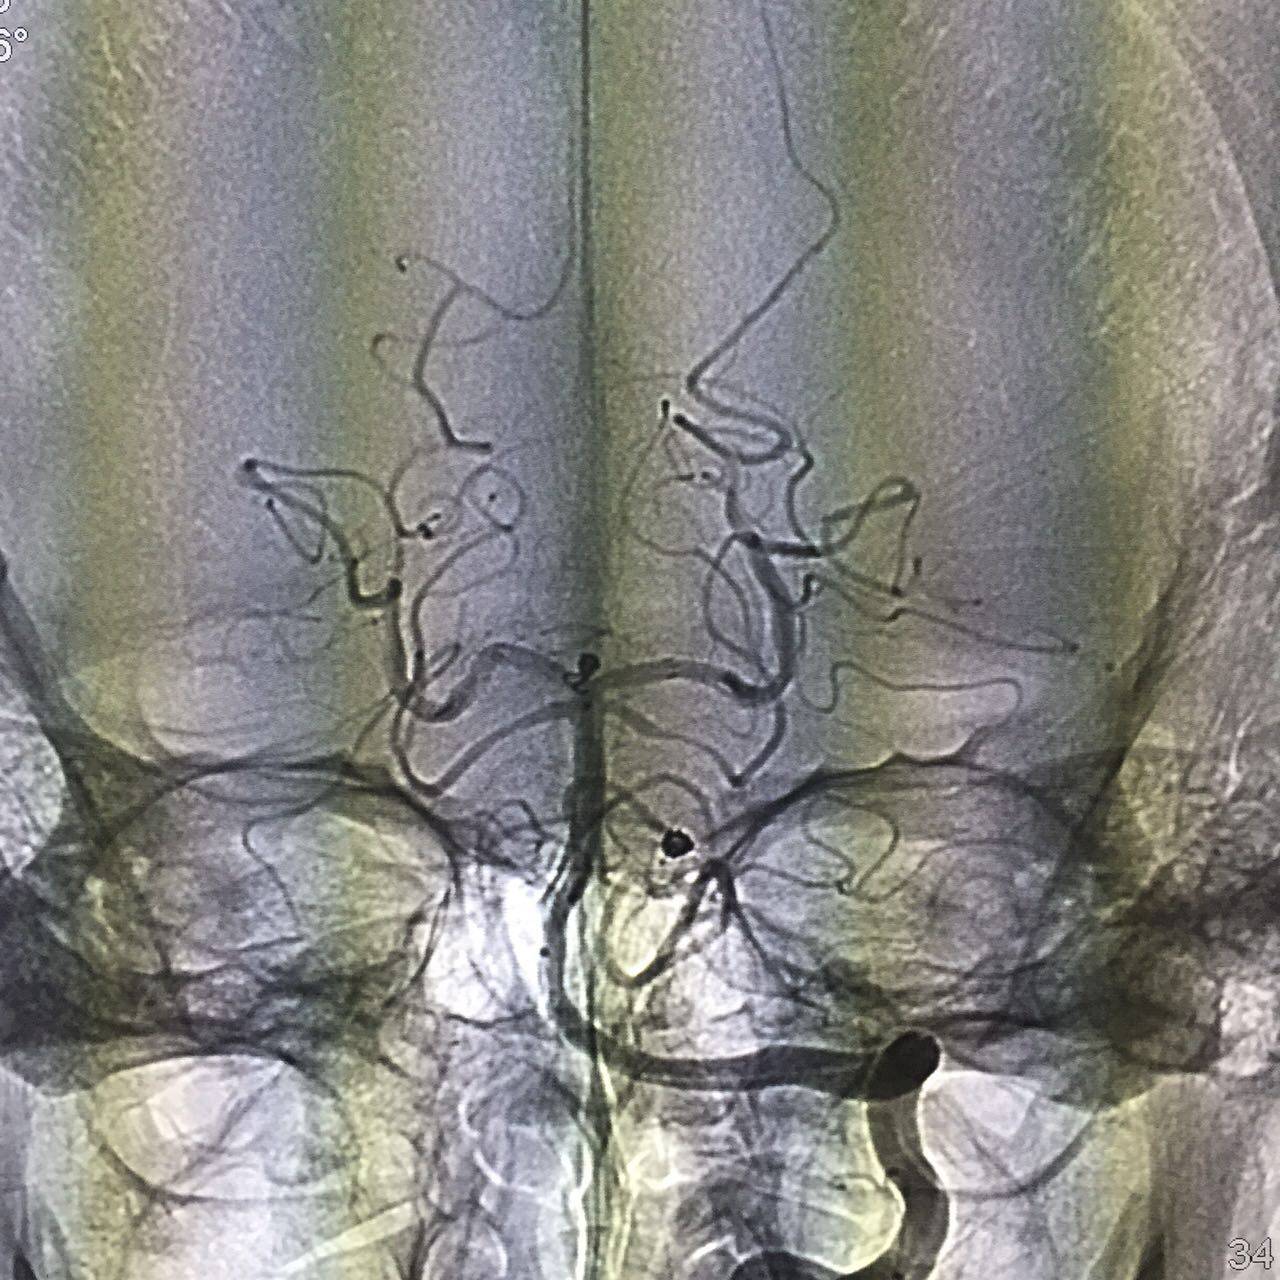

再次行左侧股动脉穿刺,引入另一根指引导管进入右侧颈内动脉,将一根Prowler Select Plus支架导管通过右侧颈内动脉、后交通动脉、右侧大脑后动脉到达左侧大脑后动脉P2段。再将SL-10微导管通过置入左侧椎动脉的另一根指引导管到达动脉瘤腔,选择Enterprise 4.5mmx14cm支架跨瘤颈放置,采用半释放技术,选择一枚Delta paq 1.5mmx4cm栓塞动脉瘤两个瘤囊。

动脉瘤填塞完毕后,完全释放支架保护瘤颈。

术后造影动脉瘤均未显影,载瘤动脉通畅。

三月后复查动脉瘤未复发,载瘤动脉通畅。